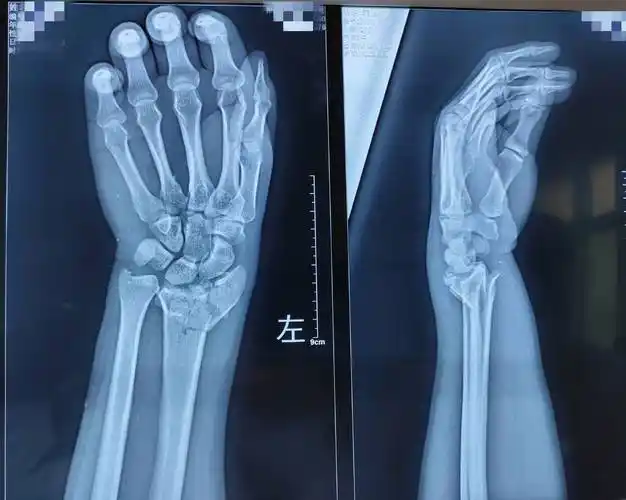

男孩,7岁,左桡骨远端骨折

桡骨远端粉碎性骨折

桡骨远端骨折